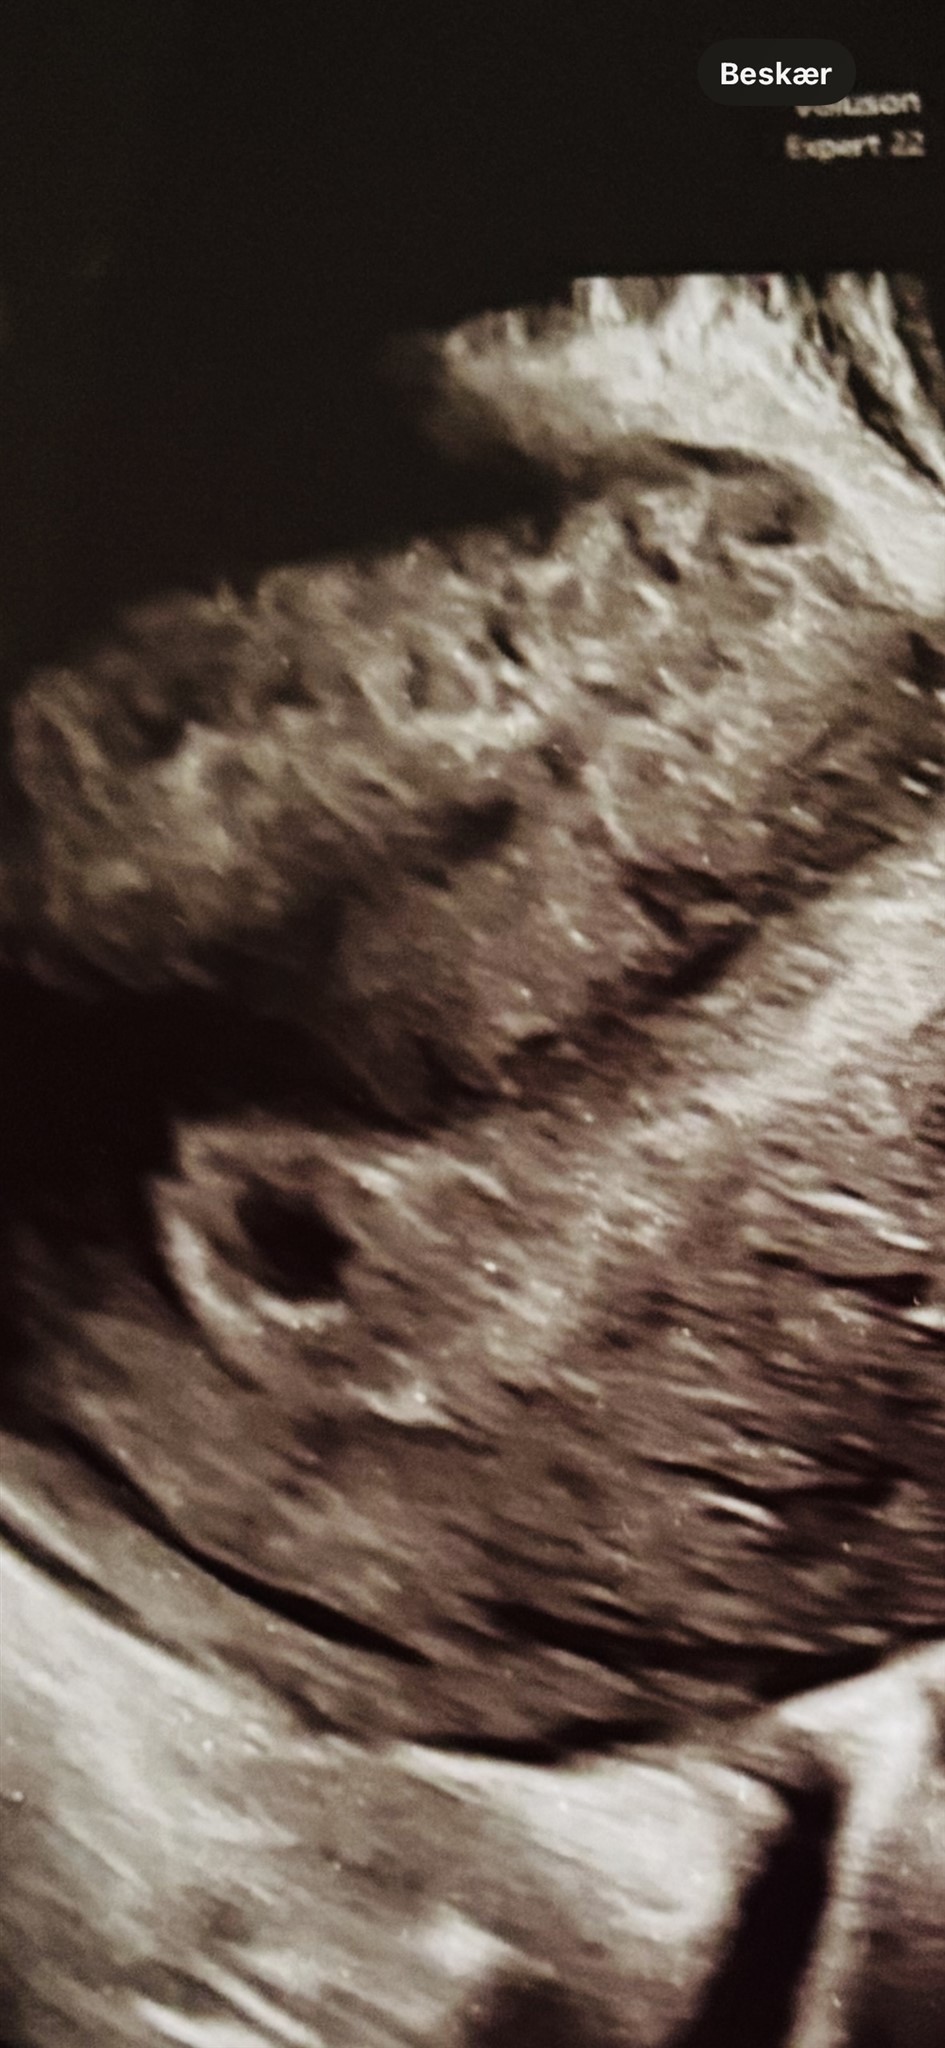

Jeg var til scanning idag og gik derfra med en lidt underlig følelse - for hende som scannet mig, sagde det godt kunne være tvillinger - dog virket hun meget usikker.

Jer som har været til tidlige scanninger - vil i mene der er to sække her, eller ligner det noget andet? Når hun gik tæt, var de begge samme størrelse, eneste forskel var at den ene sæk havde en skarper kant rundt om sækken - har desværre kun det her ene billede.

Vedhæftede fotos (klik for at se i fuld størrelse)